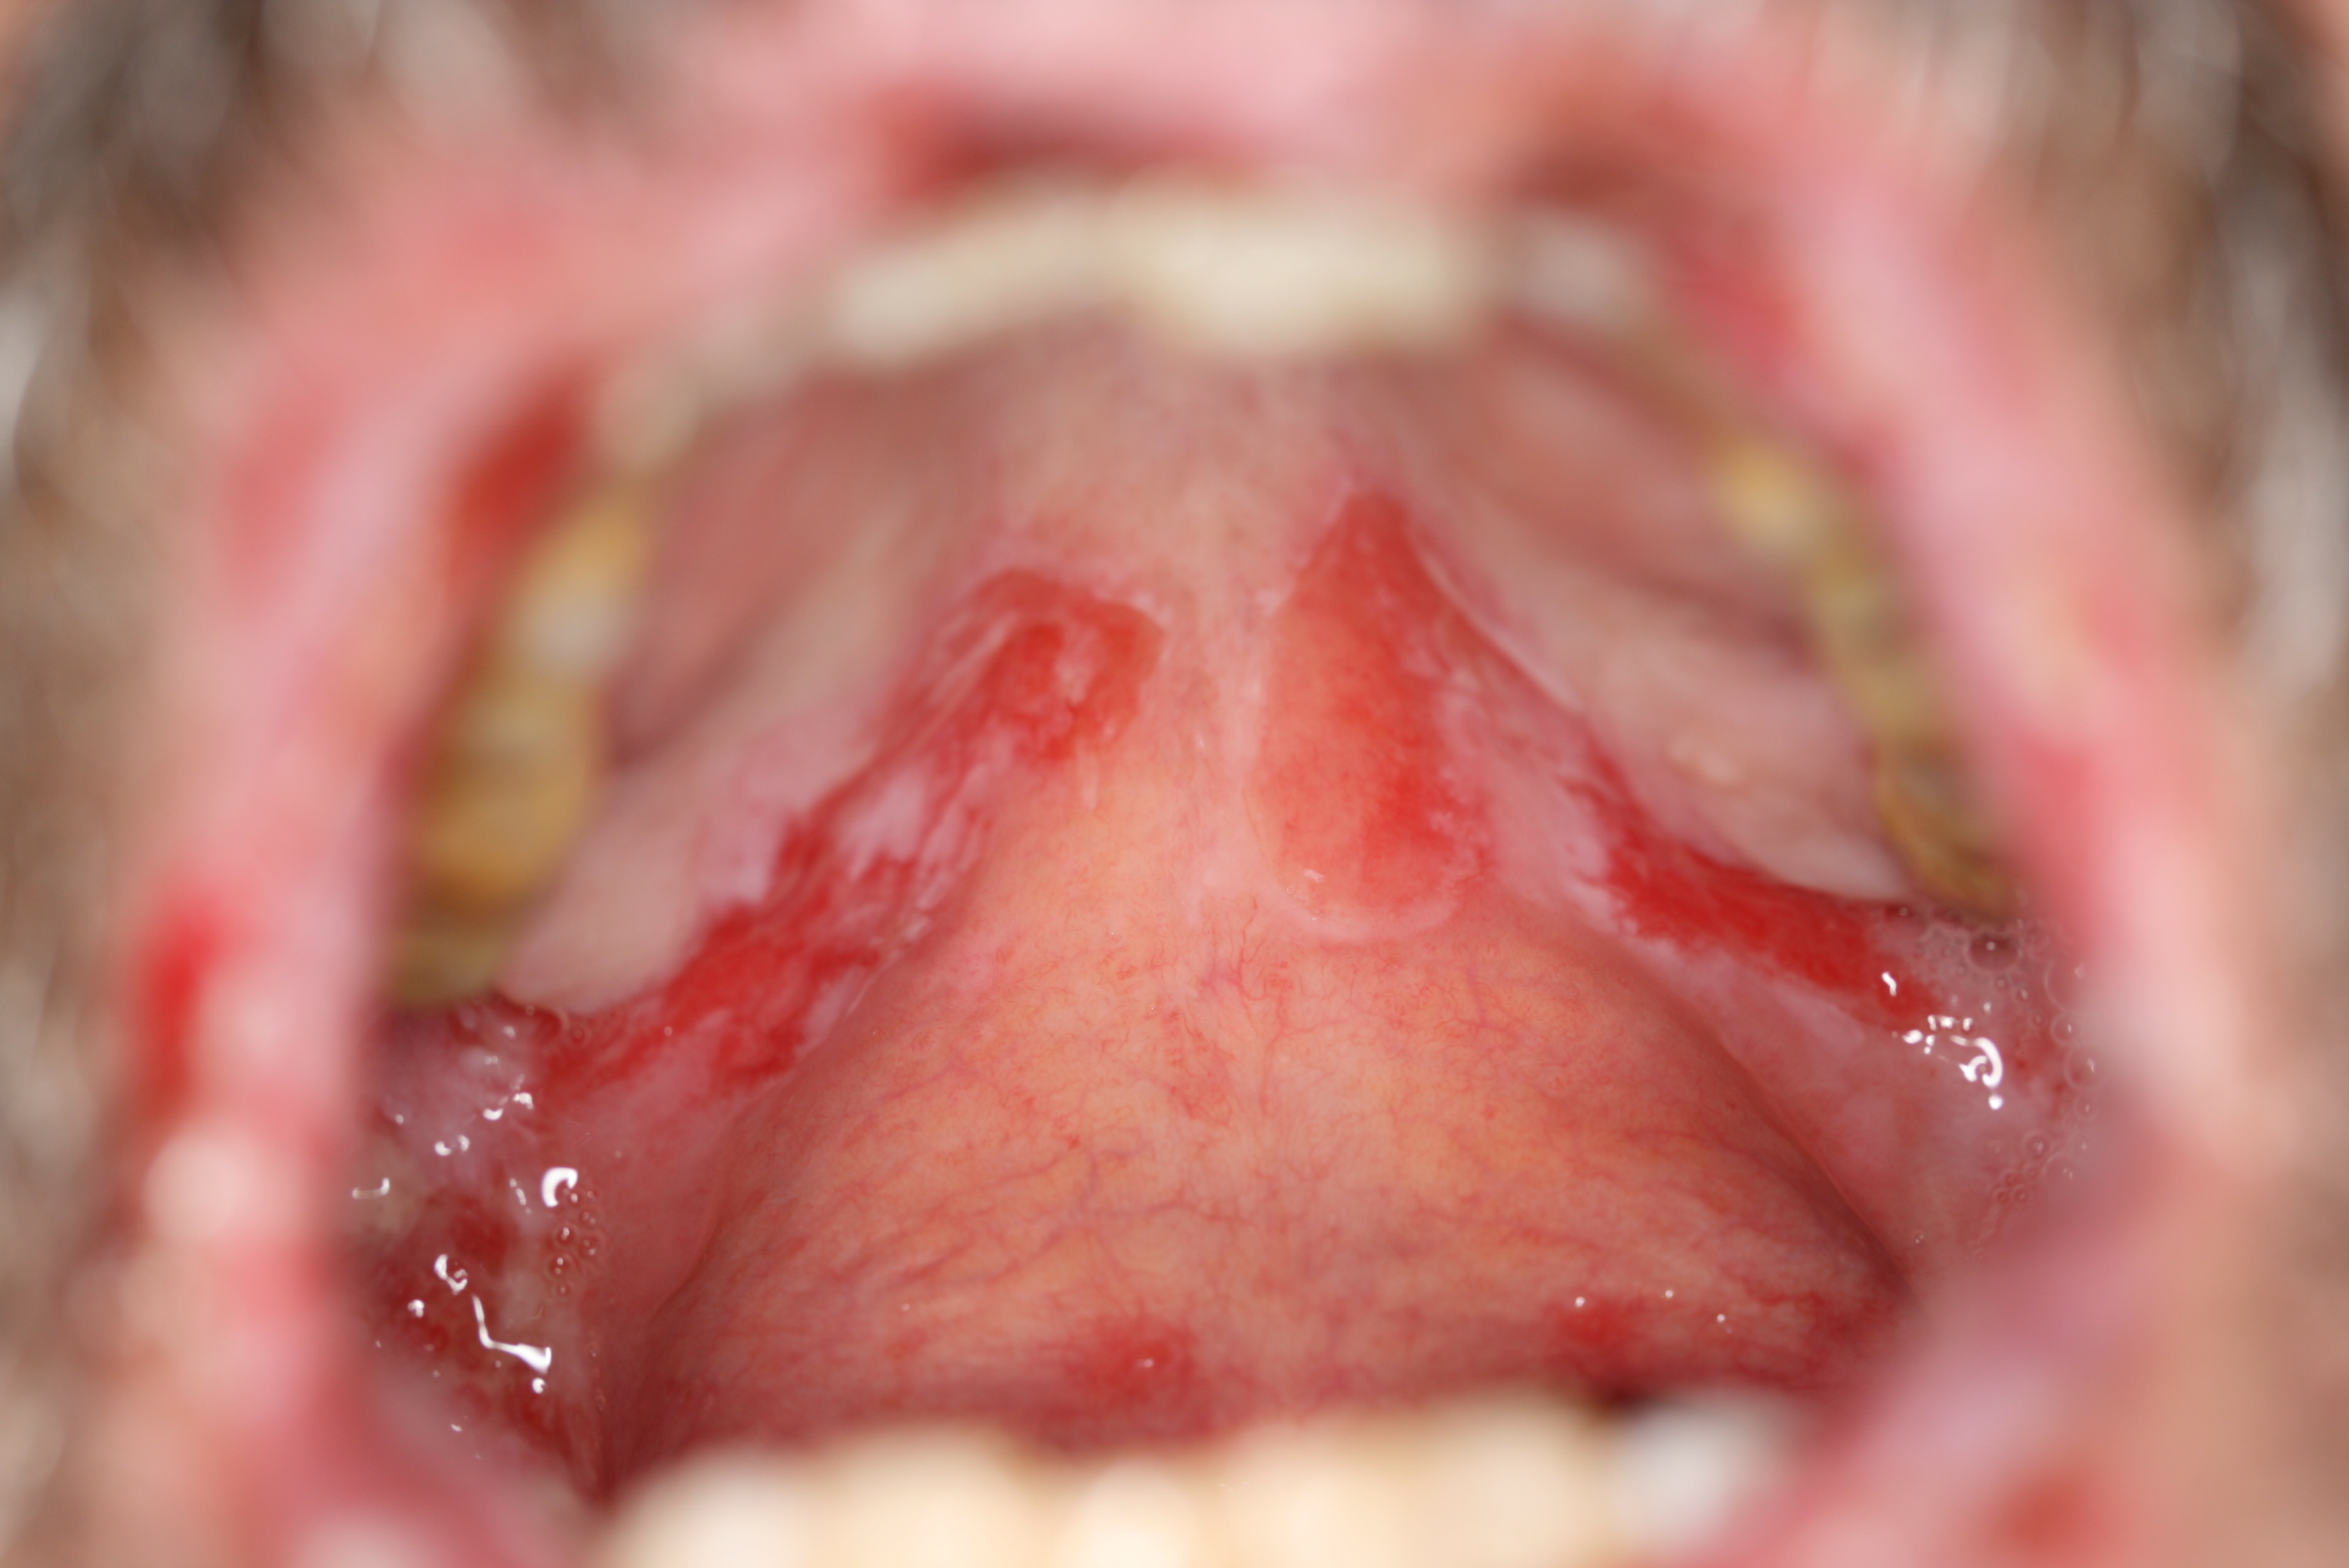

Pemfigus, mund

Sjælden hud- og slimhindesygdom, hvor der fremkommer små slappe blærer på læberne, og hud og slimhinde løsner sig. Her ses et nærbillede af slimhinden i munden ramt af pemfigus og et billede af hel mund med pemfigus.

Foto venligst udlånt af Danderm